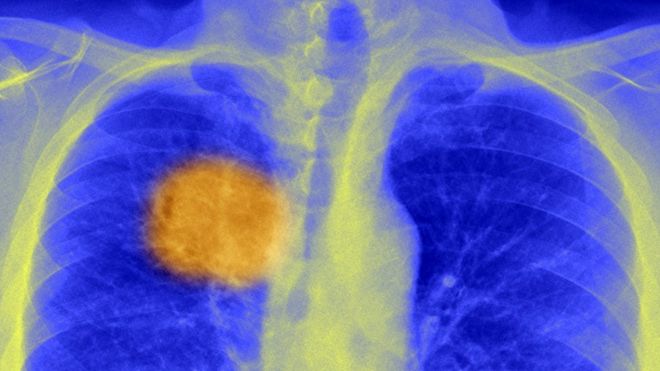

Ata besojnë se duke analizuar ADN-ën, do të kenë mundësi të zhvillojnë trajtimin e duhur. Njerëzit janë përpjekur edhe më parë të përgatisin sistemin imunitar që të luftojë tumoret, por vaksinat nuk kanë funksionuar. Problemi është se tumoret nuk përbëhen nga qeliza identike, ata janë mutacione, lëmshe gjenetike dhe mostra nga vende të ndryshme brenda një tumori, që duken dhe veprojnë shumë ndryshe.

Ata rriten pak a shumë si një pemë, me trungun bërthamë të mutacioneve, dhe pastroj këto mutacione shpërndahen në të gjitha drejtimet. Kjo njihet ndryshe si heterogjeniteti kanceroz.

Shkencëtarët besojnë se kanë gjetur trungun e këtyre mutacioneve që ndryshojnë antigjenet (proteinat që dalin nga sipërfaqja e qelizave kancerogjene).